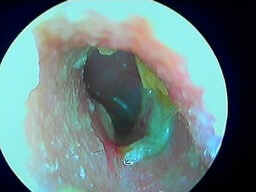

Otite externe bactérienne: pus devant le tympan

Souvent liée aux baignades (piscine, mer), l'otite externe est très fréquente chez l'adulte surtout l'été. Une douleur vive est associée à une oreille bouchée (souvent du cérumen était présent avant l'otite externe). On trouve alors du pus dans le conduit auditif externe devant le tympan. Le traitement consistera à mettre des gouttes d'antibiotique dans l'oreille uniquement et éviter de mettre de l'eau dans l'oreille durant tout le traitement (8 à 10 jours).